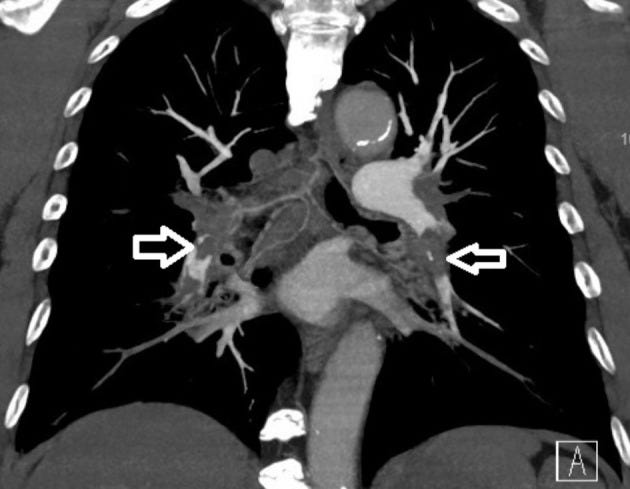

This man got the ‘first dose of the Moderna mRNA-1273 vaccine 5 weeks prior to this episode.’ He presented to emergency department with ‘progressive shortness of breath for 5 days. A physical examination revealed blood pressure of 120/70 mmHg, heartbeat of 102 beats per min, and SpO2 around 90%. Resting 12-lead electrocardiography revealed sinus tachycardia and a typical S1Q3T3 pattern. Laboratory data showed normal platelet count, hemoglobin and fibrinogen levels. A SARS-CoV-2 polymerase chain reaction was negative. The D-dimer level was 4895 ng/mL, and chest computed tomography angiography showed bilateral saddle pulmonary embolism.’

Bilateral pulmonary embolism noted on computed tomography angiography (white open arrows).